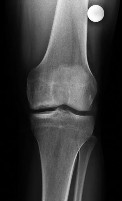

A 40-year-old pedestrian is struck by a motor vehicle, sustaining a severe valgus force to the knee. Computed tomography reveals a pure central depression fracture of the lateral tibial plateau, with the lateral cortical rim remaining intact. According to the Schatzker classification system, how is this fracture pattern classified?

Options:

- Schatzker I

- Schatzker II

- Schatzker III

- Schatzker IV

- Schatzker V

Correct Answer: Schatzker III

Explanation:

Schatzker III fractures are pure central depressions of the lateral tibial plateau without an associated split of the lateral margin. Schatzker I is a pure wedge split of the lateral plateau. Schatzker II is a split-depression of the lateral plateau (most common). Schatzker IV involves the medial plateau. Schatzker V is a bicondylar fracture with intact metaphyseal-diaphyseal continuity. Schatzker VI involves metaphyseal-diaphyseal dissociation.